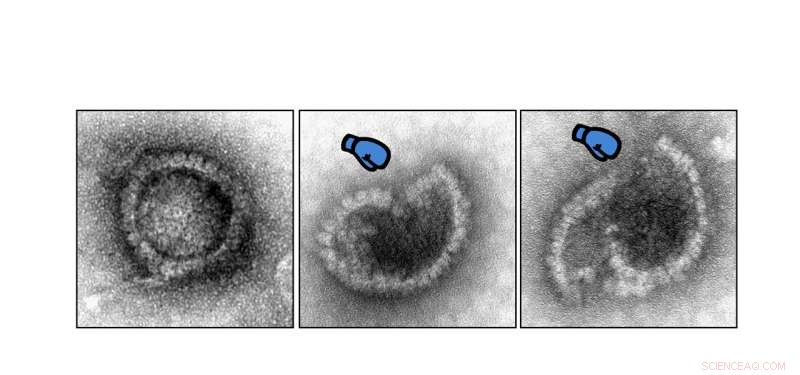

An electron microscope image. It shows how the herpes virus is attacked by the protein MxB. Credit: Manutea Serrero & Beate Sodeik, Virology, Hannover Medical School, Germany.

"Using biochemical experiments, we were able to show for the first time that MxB has the amazing ability to attack and disassemble the highly stable protective capsids of herpes viruses. The capsids enclose the genome of the viruses and thus protect it from the cell's own defense," says Professor Sodeik. The work was done with herpes simplex viruses, which trigger lip and genital herpes, among other things, and with varicella zoster viruses, which cause chickenpox and shingles. In further studies, the effect of MxB on the capsids of other herpes viruses is now being investigated, for example on the cytomegalovirus and the Epstein-Barr virus.